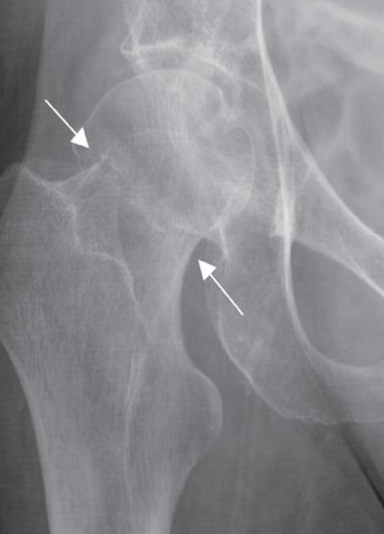

Impacted femoral neck

fracture (arrows) causing only a

sclerotic line and disruption of

the trabecular architecture.

Intertrochanteric fracture

(arrows) between the greater

and lesser trochanters